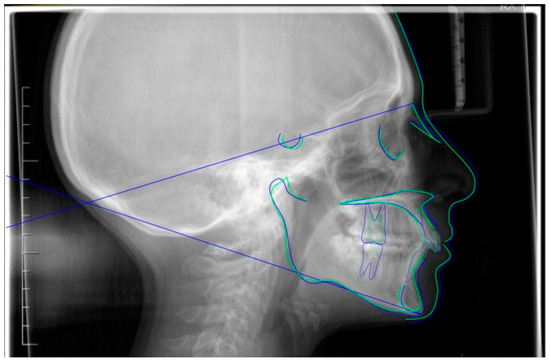

Figure 9.

Superimposition of pre- (blue) and post- (green) cephalometric traces (reference plane SN) with appropriate function on the Cephio platform.

A case of CA therapy without attachments and without the aid of hybrid elements has been documented. The patient, an 18-year-old woman at the beginning of treatment (October 2021), signed written informed consent to orthodontic treatment and authorized the use of her anonymized treatment data, including photos, X-rays and virtual models of the dental arches. She needed to rehabilitate two edentulous areas corresponding to first maxillary and mandibular molars, both on the left side, assessed as irrecoverable for destructive caries at the time of the orthodontic evaluation (Figure 1). The patient refused rehabilitation with prosthetic implants and orthodontic treatments with fixed or hybrid fixed-removable therapy. Orthopanoramic (Figure 1) and lateral teleradiography of the skull (Figure 2) were acquired to make the necessary assessments. The cephalometric examination was performed using the Cephio© Cephalometric Analysis artificial intelligence driven platform (Cephio sp. z. o. o. [Ltd.]). Her skeletal class II malocclusion was due to maxillar and mandibular retrusion (SNA 80°, SNB° 74.6°, ANB 5.4°, SNPog 76.2°). She had “long face” (OP-SNP 21.1°), a posterior inclination of the jaw (MPGoGn- SNP 35.4°), slight hyperdivergence (FMA 26.2°), with pro-inclined lower incisors (1-NB 28.4°, IMPA 96.1°) and retroclined upper incisors (1-NA 14.1°, FMIA 57.7°). Overjet and overbite were severely altered (6 and 7 mm) (Table 3). Orthodontic treatment started 4 months after the first left maxillary and mandibular molar extractions. Intraoral and facial photos were captured (Canon© Coolpix A900, Canon, Tokyo 146-8501, Japan). Dentally, she had a first molar and canine class on the right side, and a first canine class on the left side in which the molar class was no longer assessable (initially it was a first class); however, a partial reduction in edentulous spaces was observed due to the movement of adjacent teeth (Figure 3) and lower incisors were moderately crowded. Precision silicone impressions (Elite HD+ Putty Soft Normal and Elite HD+ Super Light Body, Zhermack SpA, Badia, Italy) were taken using the double technique. Then, a virtual setup of the treatment with CAs was developed to evaluate its feasibility. It showed full closure of edentulous spaces and was also discussed successively with the patient. The orthodontist clarified there were no data from the literature (at that time) to support the successful movements required with only CAs. The orthodontist and patient started treatment by agreement. The informed consent to treatment was signed. It also covered clinical re-evaluation with solutions less favorable to the patient’s preferences if the results in the middle of treatment had been clinically unsatisfactory or unfavorable. The orthodontist explained the need to intercept any treatment complications to the patient. This also related to the predictability of intermediate results for medico-legal reasons, for the mutual protection of her as a patient and of the orthodontist as a professional responsible for the therapy. Initial and final virtual models were superimposed to evaluate the movements obtained (Maestro 3D©, AGE Solutions S.r.l., Pontedera- Pisa, Italy). At the end of the therapy, new X-rays were requested and new intraoral and extraoral photos were recorded.

The setup indicated the need to treat the patient with 44 upper and 24 lower aligners, equal to 22 movements in the upper arch and 14 movements in the lower arch. The treatment required 10 months and 2 weeks. The Sorridi® system (Sorridi®, Sorridi s.r.l., Latina, Italy) used in this clinical case is a no-attachment system, which alternates weekly between two aligner thicknesses: soft (0.06 mm) and hard (0.08 mm), for each programmed movement. Soft aligners are used in the first week, then hard aligners are used for another week until the next soft-type aligner. The gingival margin is straight beyond the gingival zenith above 2 mm (Figure 5). No interproximal reduction (stripping) and divots to guide dental movements were required. No hybrid supports were programmed (corticotomies, mini-screws, elastics). No further refinements were deemed urgent. Orthodontic retainers were applied even if a slight mesio-lingual rotation of the second left lower molar orthodontically transposed in place of the missing first molar was present (Figure 6). Post-treatment radiographs were requested (Figure 7 and Figure 8) and new cephalometric analysis was performed (Table 3). The patient finished the treatment remaining in the skeletal class II from biretrusion (SNA 78.5°, SNB° 73.8°), but the unfavorable ratio between maxilla/mandible improved (ANB 4.8°). The long and hyperdivergent face pattern remained (OP-SNP 21.6°, FMA 27.5°). The mandibular inclination returned to normal values (MPGoGn-SNP 34°). Lower incisors’ inclination was corrected (1-NB 25.4°, IMPA 94.8°), upper incisors’ inclination strongly improved (1-NA 17.4°) and overjet and overbite were strongly reduced to values almost close to normal (both equal to 3 mm) (Figure 9). Pre- and post-treatment superimposition of virtual models allowed us to evaluate the extent of movements that were actually obtained (Figure 10). Furthermore, distances were measured on virtual models before and after the orthodontic treatment. The upper edentulous space (from the distal surface of the second premolar to the mesial surface of the second molar) initially measured 5.33 mm and 0.11 mm at the end of treatment, the lower one (distal to the second premolar and mesial to the second molar ipsilaterally) was 7.68 mm and it was closed completely, leaving just 0.9 mm. The distance between the cusp of the left upper canine and the disto-buccal cusp of the ipsilateral upper second molar was 29.88 mm, and then decreased to 24.33 mm with a variation in the upper intercanine distance of just 1.64 mm (from 28.31 to 29.95 mm). It indicates that much of the closure was due to mesialization of the molar as well as distalization of the lateral teeth. In the lower arch, the distance between the cusp of the left canine and the disto-vestibular cusp of the second molar decreased, going from 30.42 mm to 24.59 mm, almost 6 mm, with a variation in the intercanine distance from the initial 20.36 mm to 23.73 mm. The resolution of anterior crowding and a reciprocal movement of distalization of the canine-premolar sector and mesialization of the second molar, all equal to about half a cusp each, led to an optimal closure of the posterior edentulous space.